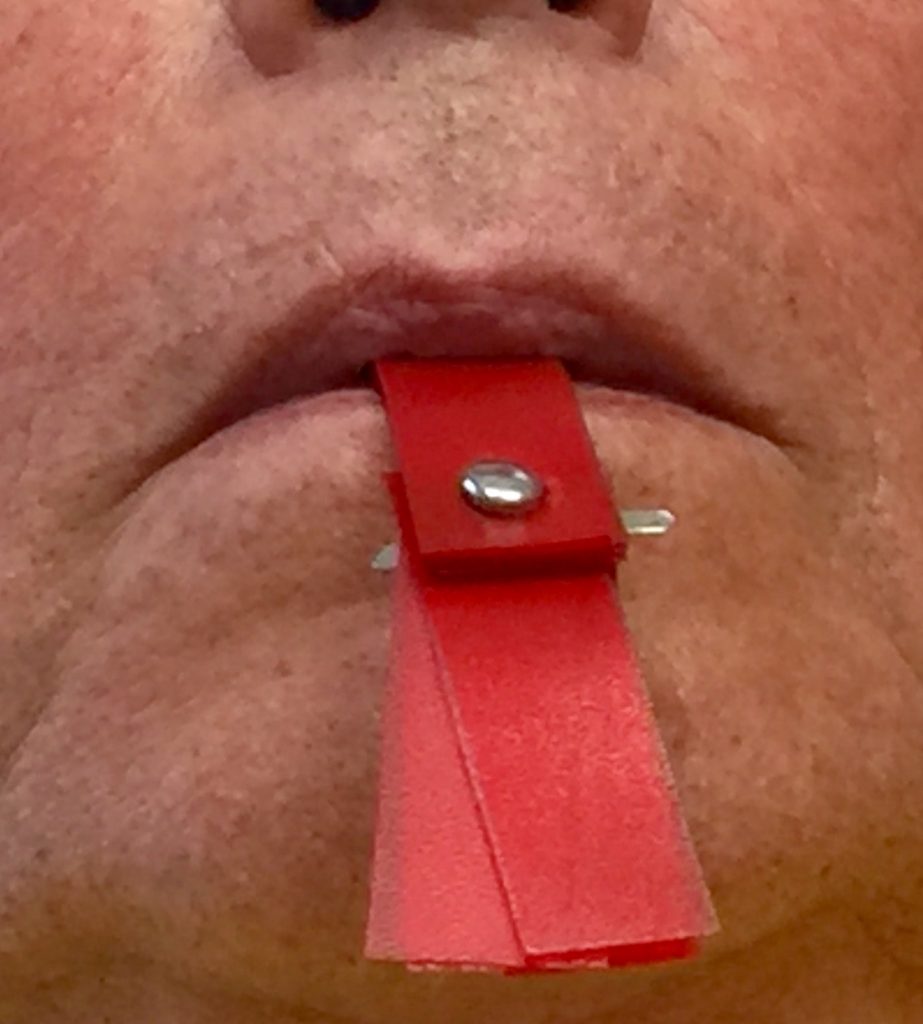

Instalación de Talla de Campo Operatorio.

Instalación de Separador Labial Quirúrgico.

Comprobación intraoperatoria de la Guía Quirúrgica.